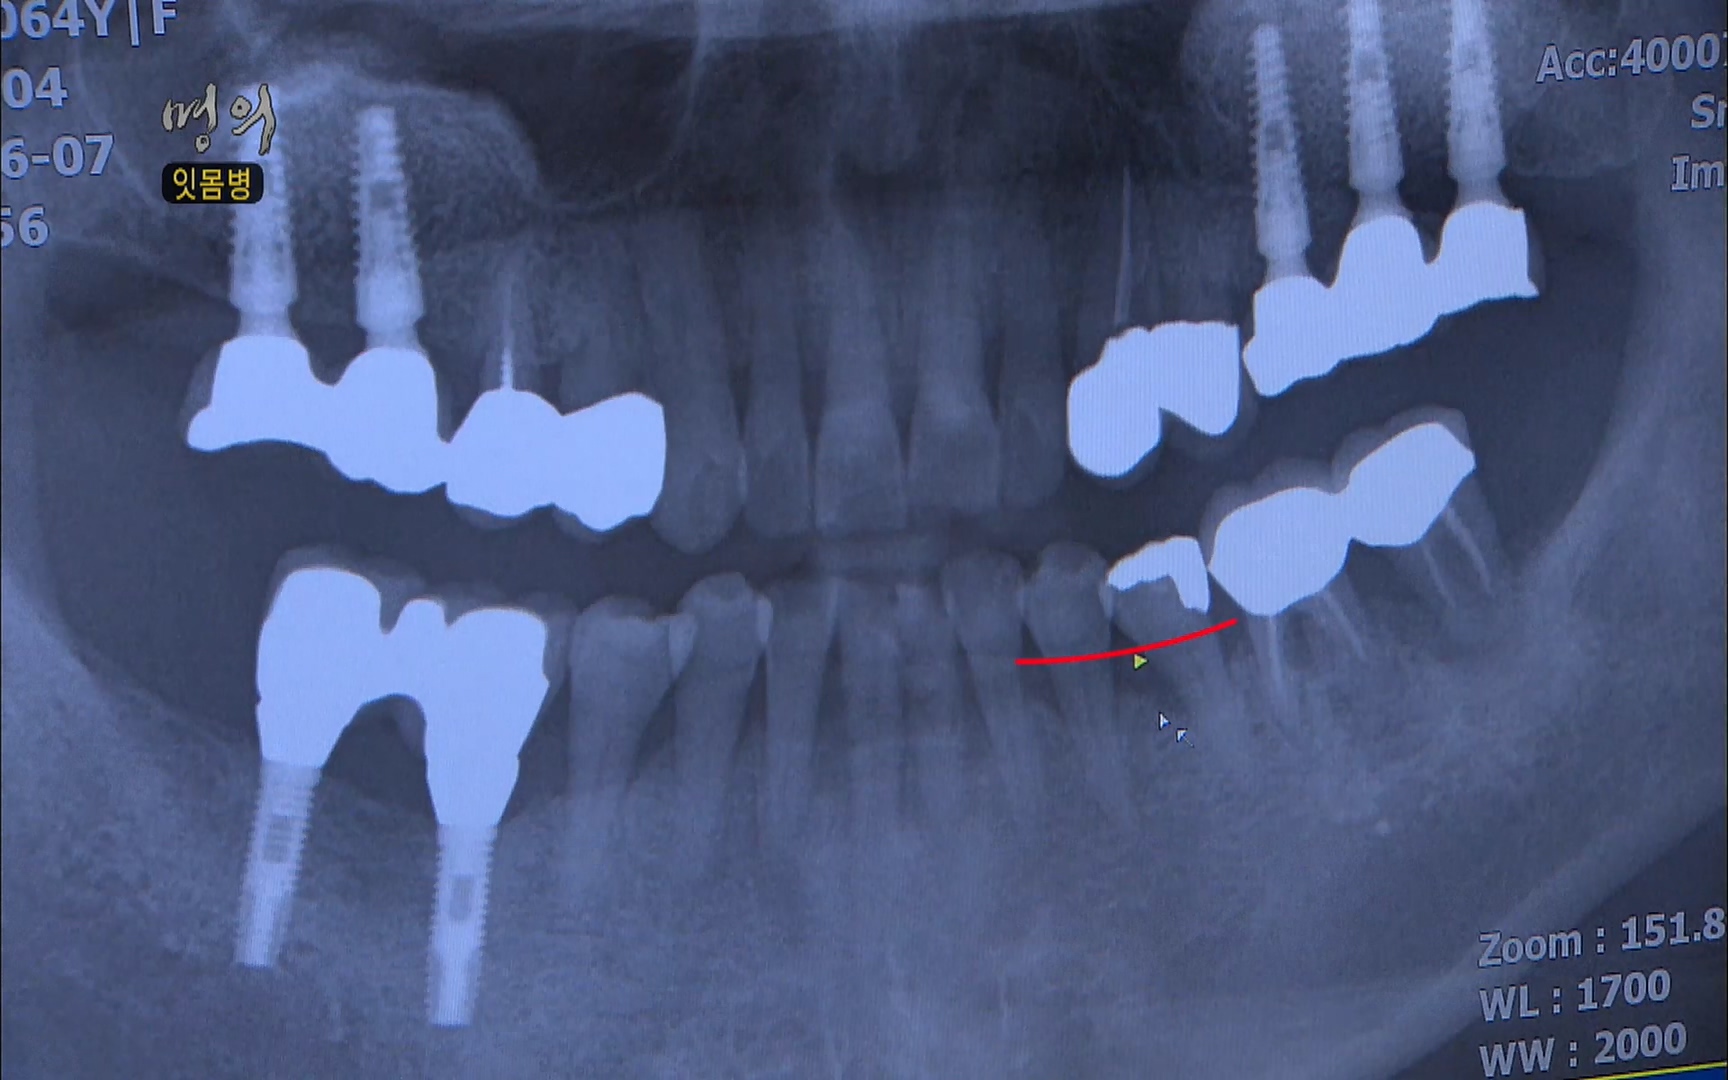

당뇨가 같이 겹치면서 잇몸뼈가 없어지는 현상이 더 가속화됐다고 볼 수 있습니다

당뇨병 환자는 세균에 대한 면역기능이 떨어지게 되고 그 염증에 대처할 수 있는 혈액순환이 잘 안 되기 때문에

지금 치주낭을 측정해보면 치주낭의 눈금의 표시가 최대 깊이가 12mm인데 최대 깊이까지 다 들어가거든요

이를 지지하고 있는 치조골의 파괴가 이미 일어난 치주염 환자는